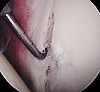

Хирургия голеностопного сустава. Группа традиционных и артроскопических вмешательств в кости, хряще, связках и капсуле этого анатомического образования. Произведено при свежих травматических поражениях, длительных последствиях поражений, воспалительных и дегенеративно-дистрофических заболеваниях суставов. Целью операций на голеностопном суставе является устранение или предотвращение прогрессирования патологического процесса, максимально возможное восстановление функций сустава. Вмешательства чаще всего выполняются обычно под кондуктивным наркозом.

Показаниями к открытой операции или артроскопическому вмешательству в голеностопном суставе в травматологии являются хроническая боль неизвестного происхождения, артрит, синовит, хондромаляция, наличие костных спаек и волокнистых спаек, а также свободные органы в суставной полости. В перечень противопоказаний к вмешательству входят тяжелые сопутствующие заболевания, распространенные острые инфекционные заболевания, локальные очаги кожных инфекций в области суставов.